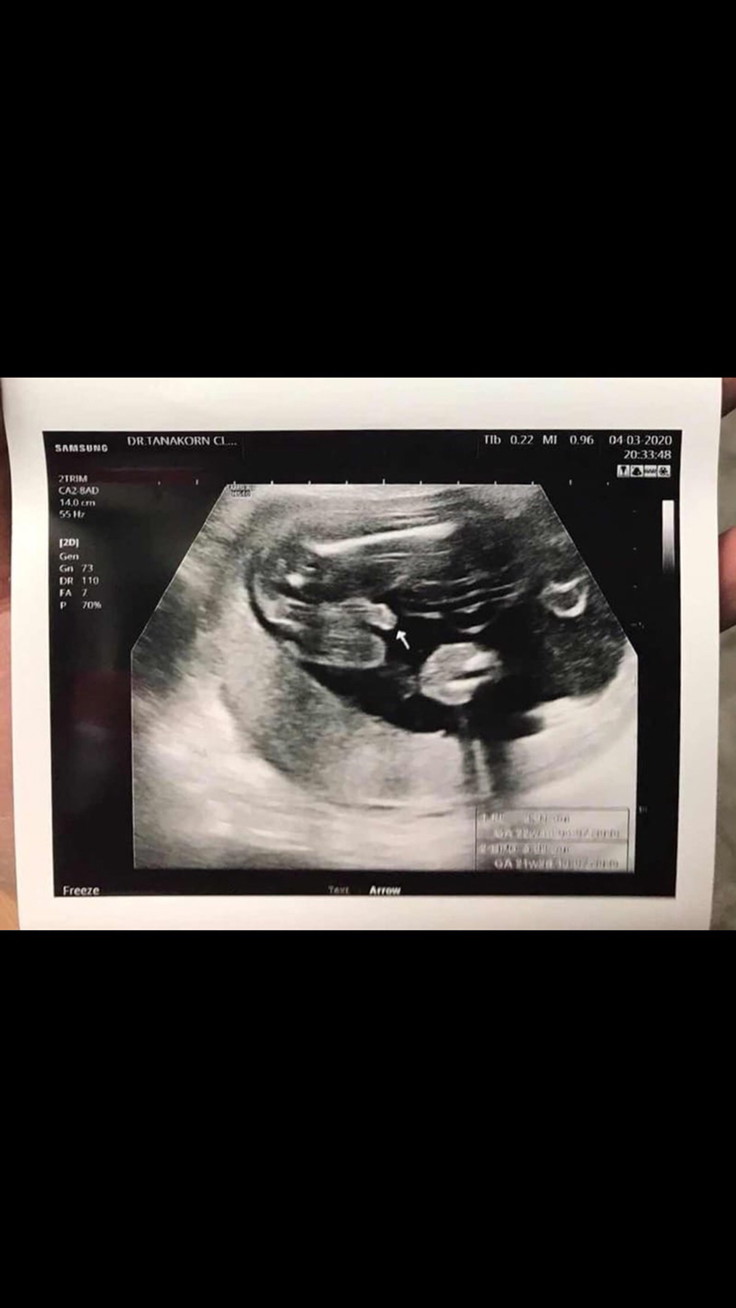

ตรงลูกศรเลยค่ะ

ชี้โด่มาเลยจ้า

ปึ๋งปั๋งมากค่ะ